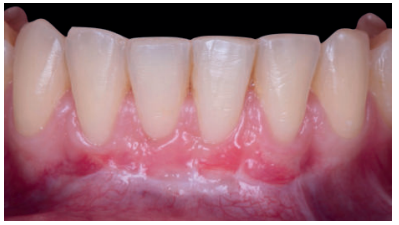

El control a la semana (Figura 13) presentaba inflamación moderada y a las 2 semanas (Figura 14) se retiraron los puntos de sutura. La paciente acudió a los 4 meses (Figura 15) y al año (Figura 16) a visitas de revisión, donde se apreció una buena banda de tejido queratinizado y una pequeña cicatriz.